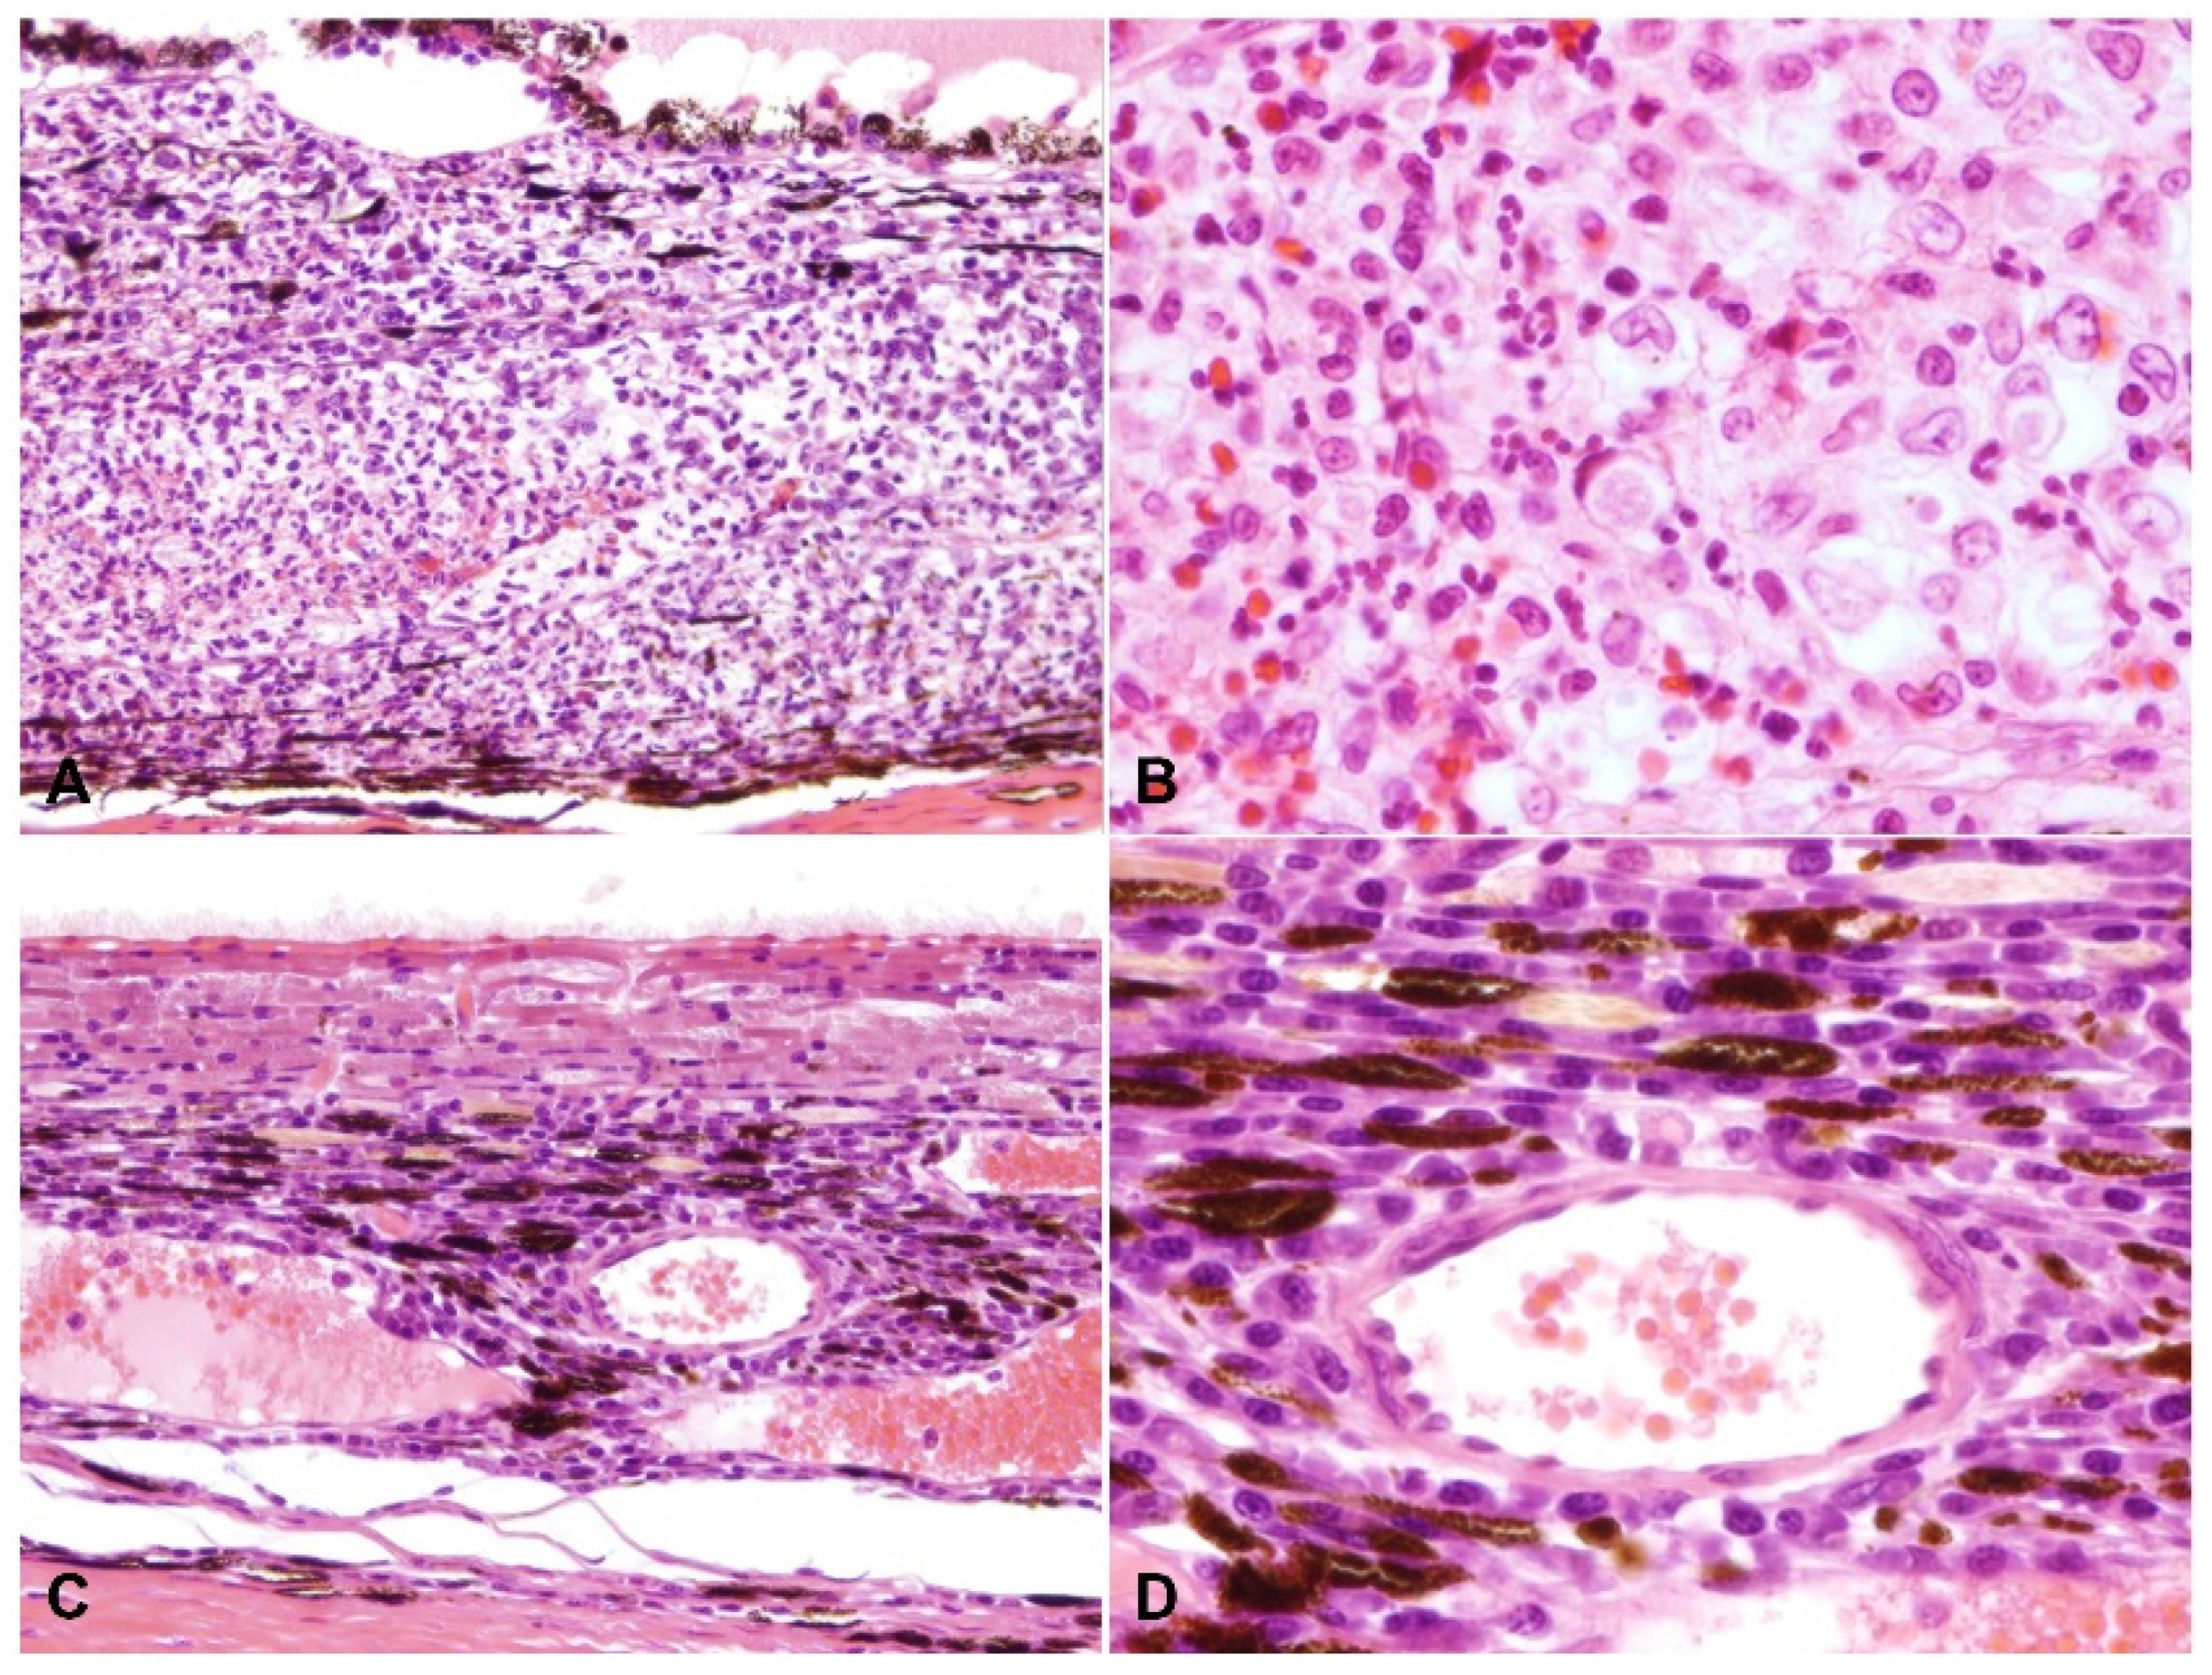

Figure 5.

Retinitis. H and E: (A) pyogranulomatous vasculitis, with thrombosis, perivascular edema, fibrinous exudation and vascular and perivascular infiltration of macrophages, plasma cells and neutrophils (200× total magnification); (B) there is perivascular lymphoplasmacytic infiltrate; note the marked proteinaceous exudate in the posterior segment (asterisk, 200× total magnification); (C) there is retinal detachment with subretinal exudate (asterisk) and hypertrophy (“tomb stoning”) of the retinal pigment epithelium (arrow) (200× total magnification).

A total of 9 of the 30 cases (30.0%) had vasculitis, 8 of which consisted of pyogranulomatous infiltration of the vessel wall (Figure 3 and Figure 5), with the remaining cases characterized by plasmacytic infiltrate (Figure 6). Regardless of the infiltrate, all lesions of vasculitis included fibrinoid degeneration of the vessel walls, with plump activated and/or necrotic endothelial cells. Vasculitis was noted in the episcleral vessels in five cases: in the choroid, ciliary body, and retina in four cases each and in the iris in two cases.